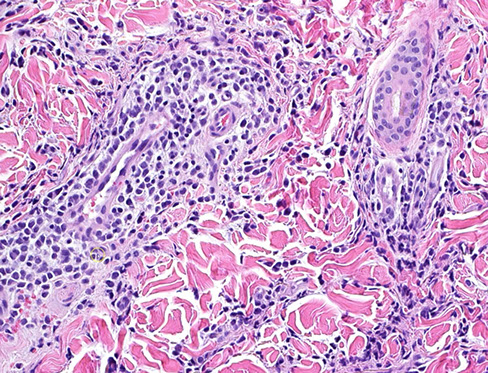

Syringocystadenoma Papilliferum (SCAP)

aka papillary syringadenoma

b9 sweat gland proliferation that arises in the middle of a nevus sebaceus

- warty tumor of scalp, neck, and face that can occur at any age

- clinically is a slow growing or recent change in a brithmark, may be crusty and start to bleed

- 1/3 have adjacent nevus sebaceus, 10% with adjacent BCC

- malignant counterpart is syringocystadenocarcinoma papilliferum

Micro: glandular papillary prolif connected to skin surface

- has ducts that look similar to sweat ducts sometimes, which are lined by cuboidal cells, that eventually empty to skin surface

- dense plasma cell infiltrate in the dermis, or in the middle of the papillary structures